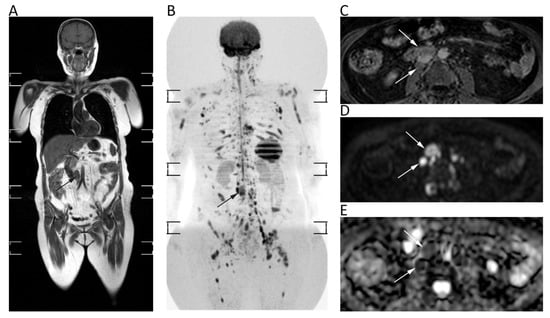

11. Prostate

| Lymph Nodes and Spleen | Albano, D.; et al., Eur. J. Radiol. 2016 [87] | Prospective; 68 patients with FDG-avid lymphoma. Comparison between WB-MRI with DWI and FDG-PET/CT. 1.5T MRI. | Excellent agreement between WB-MRI and FDG-PET/CT stage (k = 0.88; p < 0.05); WB-MRI stage was equal to FDG-PET/CT stage in 91.2% (62/68; in particular, 35/37 Hodgkin lymphoma, 27/31 Non Hodgkin lymphoma). Sensitivity of WB-MRI for splenic involvement was 100%. |